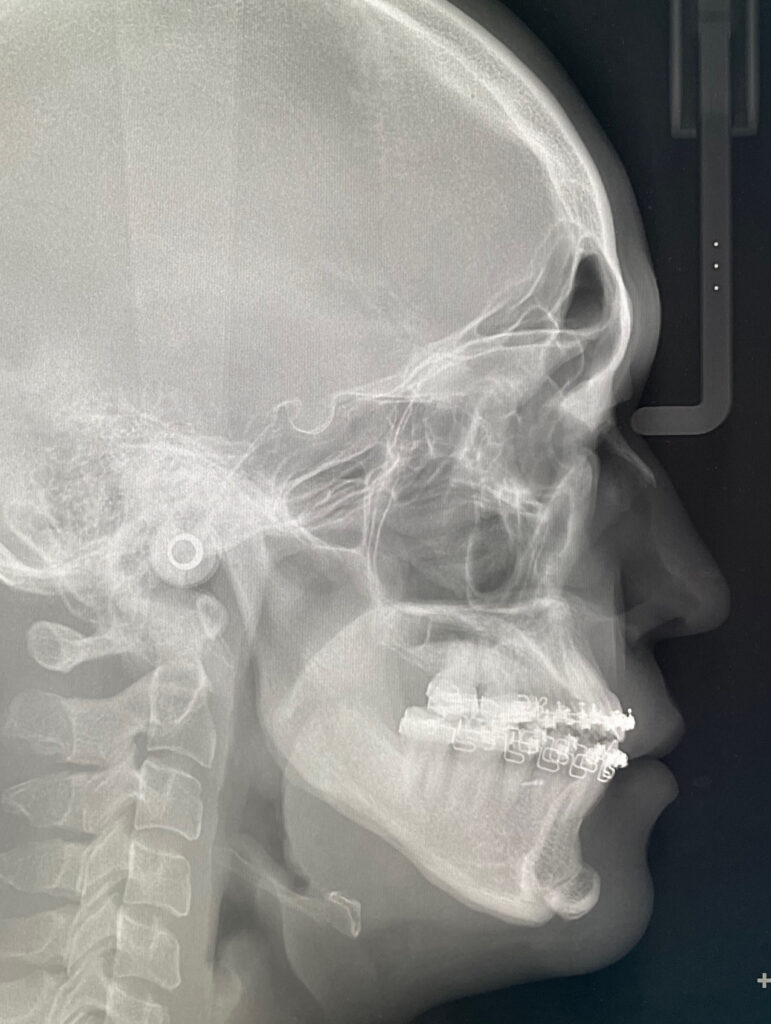

セファログラムを用いた診断

標準的な顔のバランスと比較すると、上顎はやや後方にあり、下顎は大きく前に出ていることがわかりました。そこで、上顎を少し前に出し、下顎を後ろに下げるとともに、上下の顎を一体として回転させることで、顎先の突出感を改善する計画としました。上顎は2.5 mm前方に移動し、後方を4 mm持ち上げる形で回転させる予定としました。

反対咬合は消失していて、咬合は安定しています。レントゲンでは後戻りを認めません。